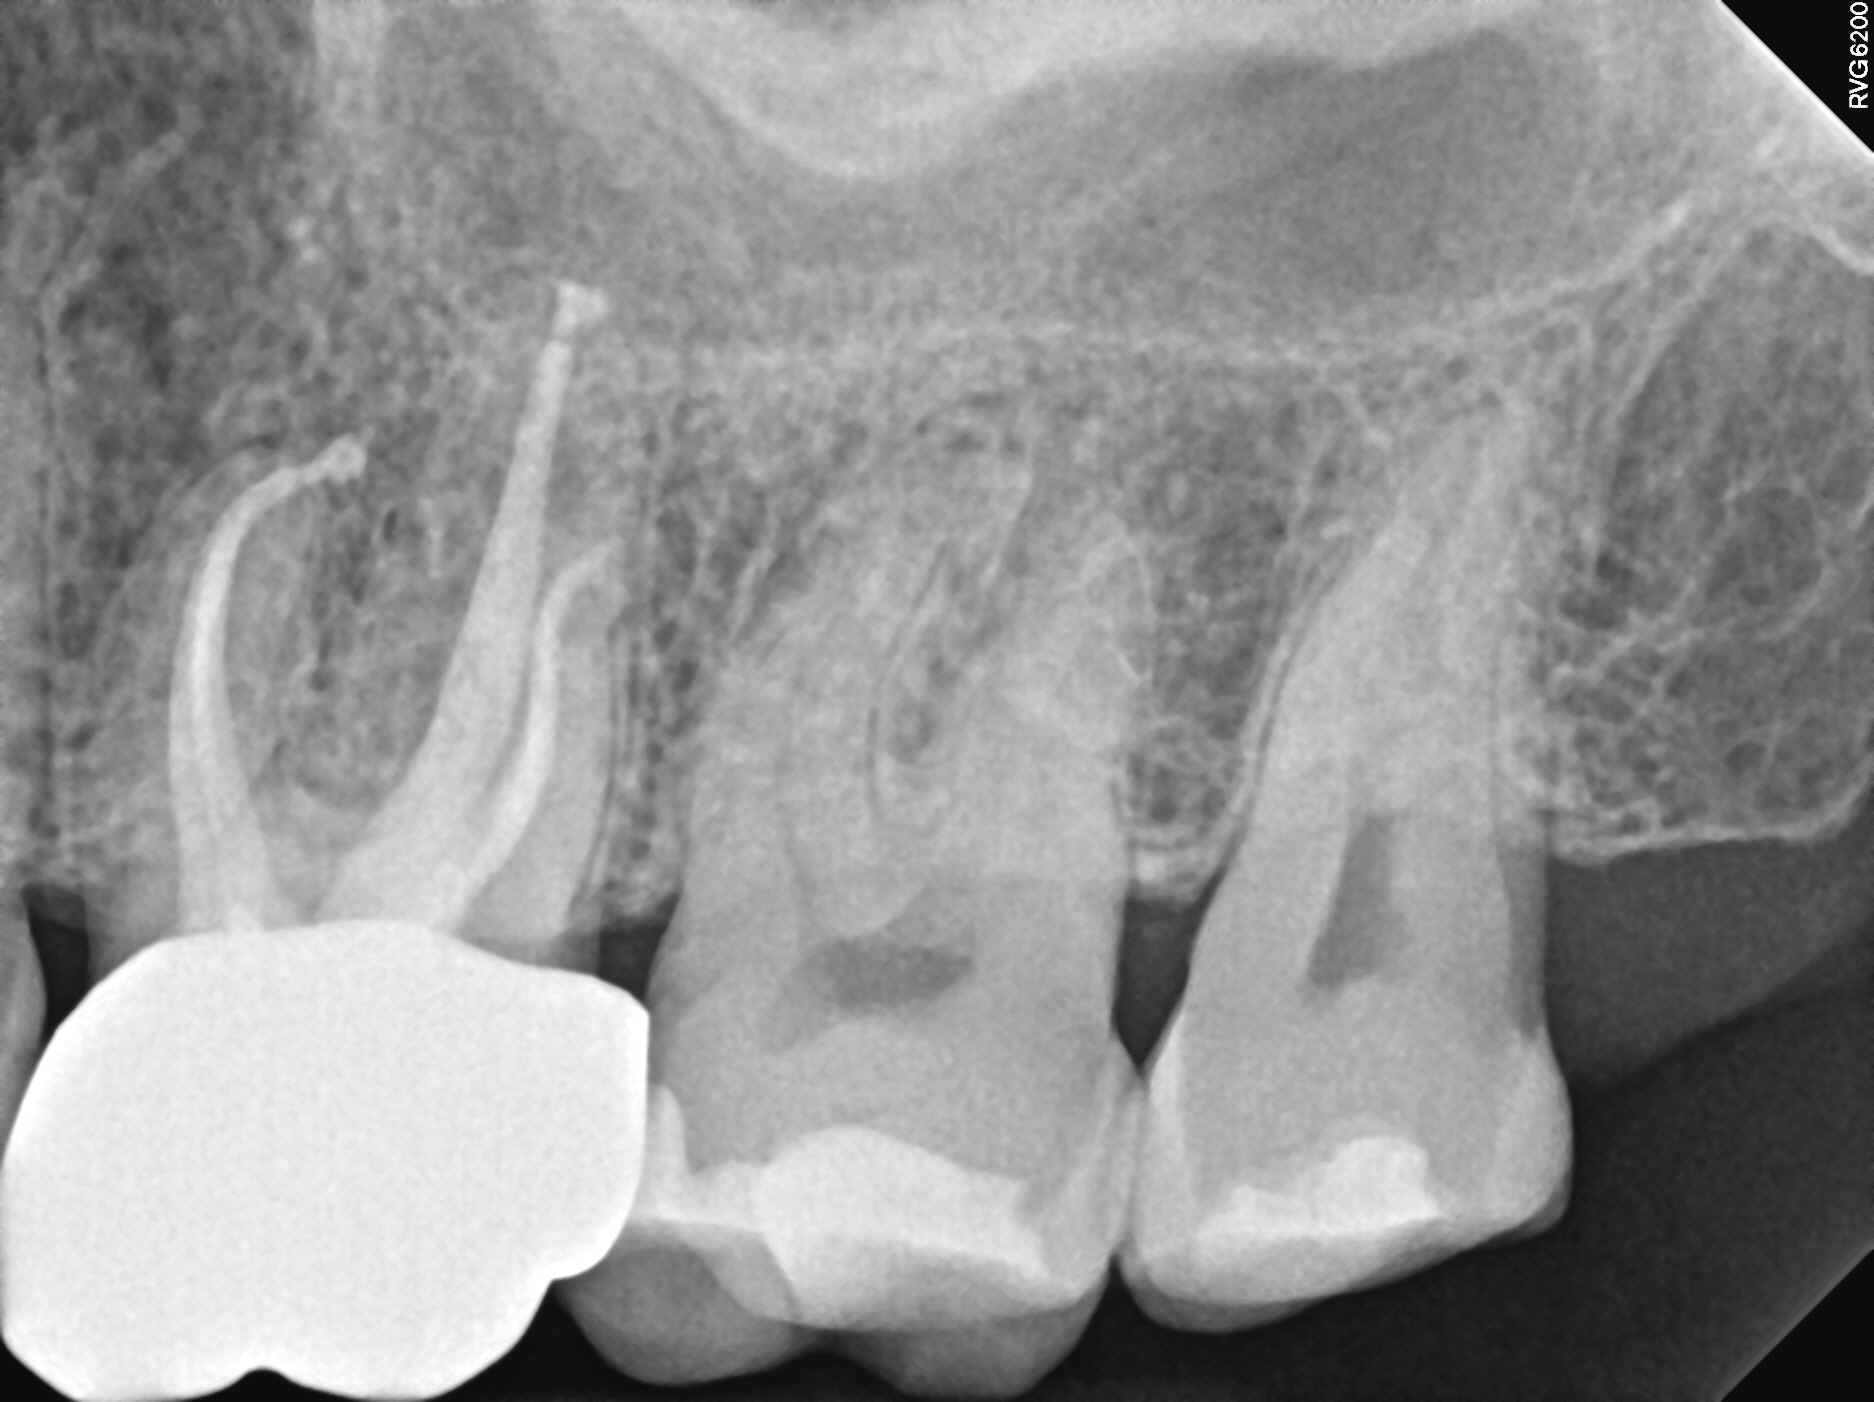

Case 9

This case shows just how curved the roots of teeth can be, which can lead to the nerve canal spaces being difficult to fully treat. These types of cases are often referred to endodontic specialists for treatment due to the added complexity of the curved roots.